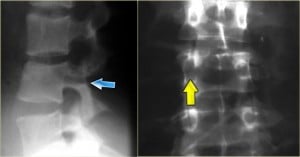

Some Radiographs

The following radiographs can give you and idea of what a chance fracture is and what is its location: